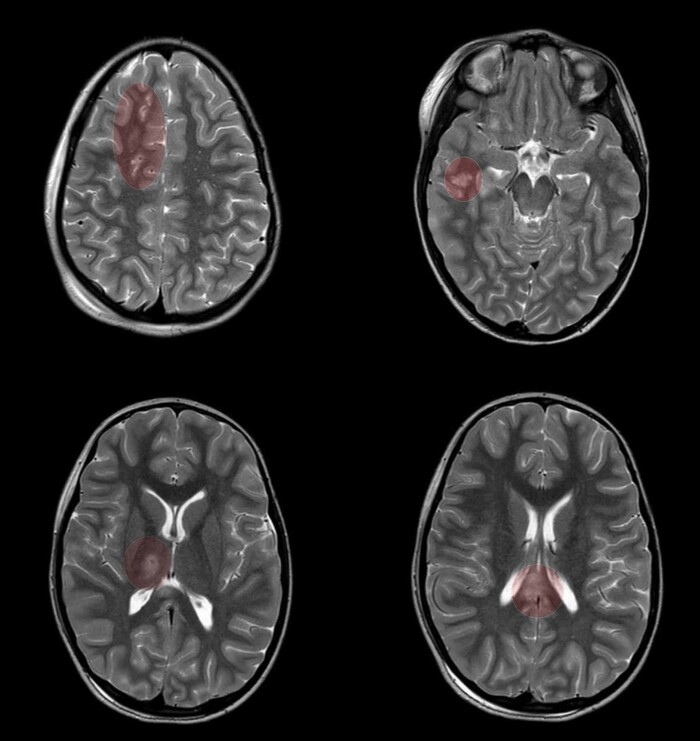

На 3й день после травмы из комы так и не вышла, посему сделали МРТ, на котором обнаружились участки повышенного сигнала на Т2-взвешенных изображениях на границе серого и белого вещества фронтально и темпорально справа, а также в область правого таламуса и в заднем отделе мозолистого тела т.н. сплениуме:

которые визуализировались и на FLAIR: